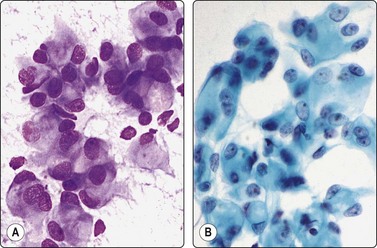

image

Fig. 13.6 Moderately-differentiated adenocarcinoma

Aggregate of malignant cells; marked nuclear enlargement and nuclear pleomorphism; nuclear crowding; microacinar pattern: indistinct cell borders. Note contrasting honeycomb sheet of benign epithelium (DQ, HP).

Fig. 13.7 Moderately-differentiated adenocarcinoma

Cellular smears of less cohesive malignant glandular epithelial cells; vesicular nuclei; prominent nucleoli. Note fragile vacuolated cytoplasm suggestive of a clear cell pattern in B (A, Pap; B, DQ, HP).

Fig. 13.8 Poorly-differentiated adenocarcinoma

Poorly cohesive malignant cells with large vesicular malignant nuclei and large nucleoli. Note small sheet of benign epithelium on right in A (A, DQ; B, Pap, HP).

In smears of prostatic carcinoma, sheets of benign glandular epithelial cells are commonly seen side-by-side with aggregates of malignant cells (Fig. 13.6), reflecting the diffusely infiltrative growth of the tumor. Benign and malignant cells can be directly compared (very helpful clue) and differences in cytoarchitectural features are easily appreciated. Nuclear enlargement is one of the most important criteria of malignancy. Nucleolar enlargement is better demonstrated in Pap-stained smears.

Absence of visible cell membranes, nuclear crowding and overlapping and dissociation of cells are other important criteria. The presence of coarse intracytoplasmic secretory granules makes malignancy unlikely, but they can occasionally be found in cells from well-differentiated adenocarcinoma. Cytoplasmic vacuolation may be seen in both benign and malignant cells. Nuclear pleomorphism and chromatin abnormalities are obvious in less well-differentiated cancers but may be subtle in well-differentiated carcinomas, rendering a definitive malignant diagnosis difficult (Fig. 13.5). Demonstration of basal epithelial cells by immunocytochemistry may be of help in the distinction between well-differentiated adenocarcinoma and adenosis or basal cell hyperplasia,5 but interpretation is more difficult than in histologic sections. Immunostaining is a useful tool for the diagnosis of prostate cancer at metastatic sites.42 Results may be conflicting in metastases of poorly differentiated carcinomas.

Moderately-differrentiated carcinoma (Figs 13.6, 13.7)

Microacini showing frank nuclear atypia,

Frequent obviously malignant irregular three-dimensional clusters,

Nuclear hyperchromasia,

Conspicuous nucleoli,

Some dissociated well-preserved malignant cells,

The smear may be overrun by malignant irregular three-dimensional clusters.

Poorly-differentiated carcinoma (Fig. 13.8)

Malignant irregular three-dimensional clusters and numerous dissociated cells,

Obvious increase of N : C ratio,

Large nuclei and nucleoli,

Intense hyperchromasia,

Rare or absent microacini with frank atypia,

Dispersed cells or naked nuclei may dominate the smear. Nuclei may be smudged. Caveat: do not mistake for high-grade lymphoma.